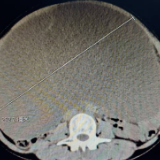

接诊的妇科主任钟雪辉一眼就注意到了异常——患者卢阿姨的肚子鼓得像足月孕妇一样,按压时还伴随着明显压痛。但卢阿姨已绝经多年,反常的“孕肚”让钟雪辉立刻警觉起来。凭借多年临床经验,钟雪辉判断卢阿姨腹腔内大概率存在异常包块,当即安排检查。结果显示:卢阿姨卵巢上长了一个25.2厘米的巨大包块。

钟雪辉团队与患者及家属反复沟通后,最终为卢阿姨实施了单孔腹腔镜下双侧附件(卵巢、输卵管)切除术。手术中抽出的囊内液高达11000毫升,相当于22瓶500毫升的矿泉水。